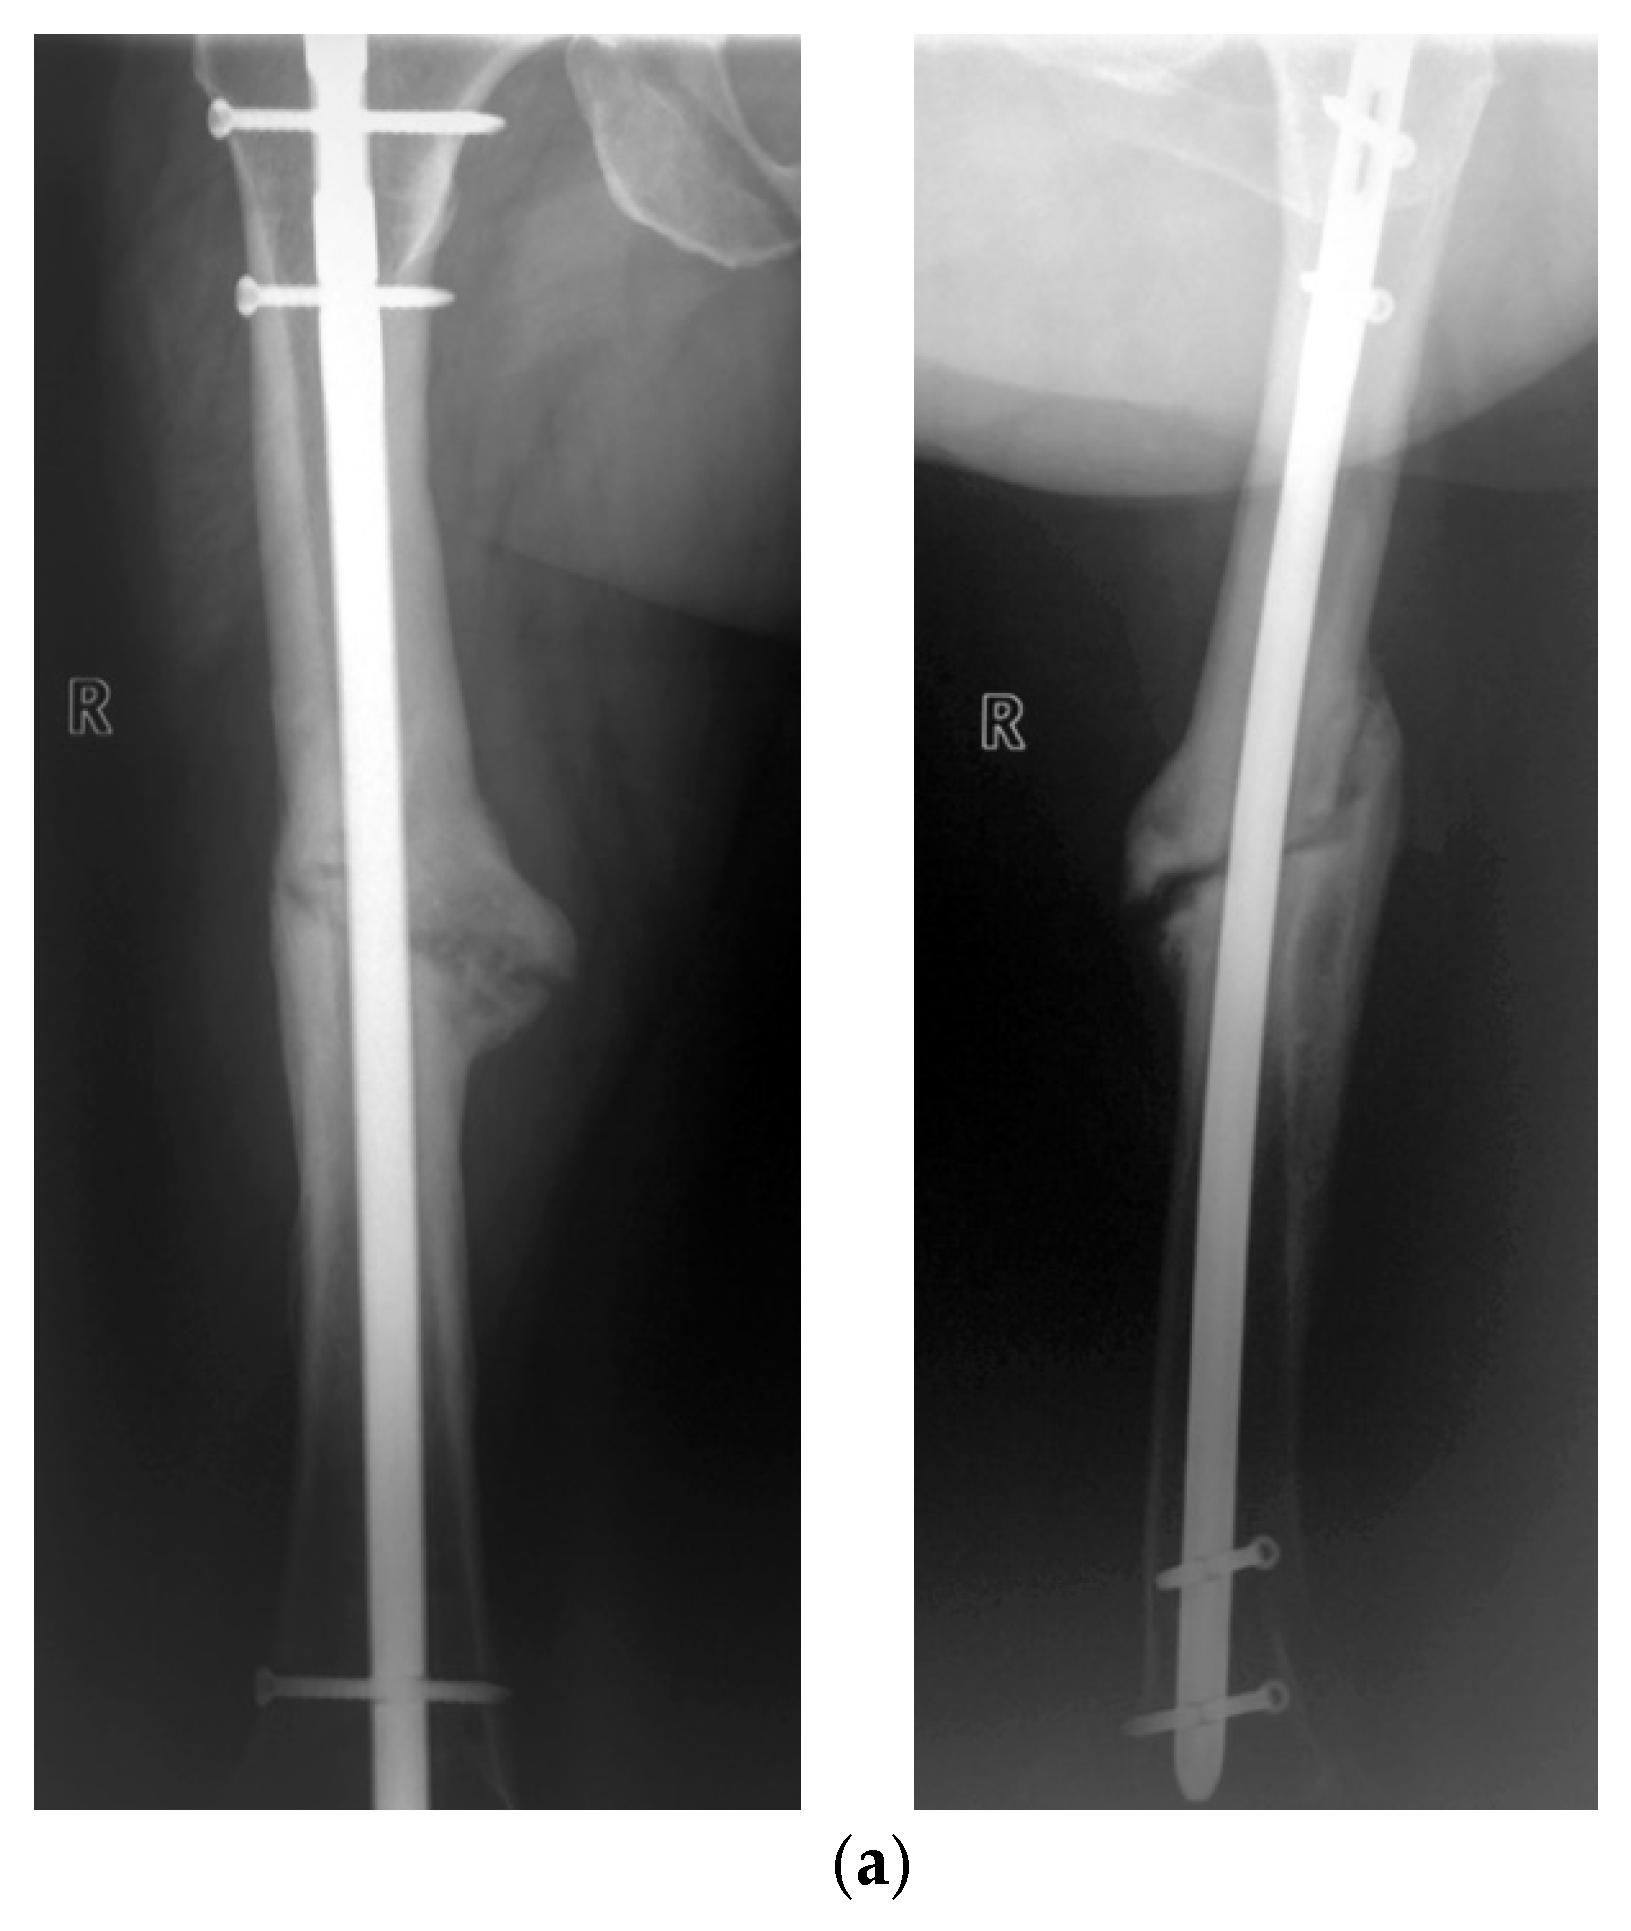

- Seide, K.; Aljudaibi, M.; Weinrich, N.; Kowald, B.; Jürgens, C.; Müller, J.; Faschingbauer, M. Telemetric assessment of bone healing with an instrumented internal fixator. J. Bone Jt. Trauma Surg. 2012, 94-B, 398–404. [Google Scholar] [CrossRef]

- Kowald, B.; Seide, K.; Auerswald, M.; Faschingbauer, M. Slow-healing non-unions. Measurement of mechanical stability with the instrumented implant. 3 case reports. Trauma Berufskrankh. 2019, 21, 181–192. [Google Scholar] [CrossRef]

- Faschingbauer, M.; Seide, K.; Aljudaibi, M.; Kowald, B.; Münch, M.; Weinrich, N.; Jürgens, C.; Moss, C.; Kirchner, R. Intelligent implants for monitoring bone healing. Trauma Occup. Dis. 2013, 15, 240–248. [Google Scholar]

- Kienast, B.; Kowald, B.; Seide, K.; Aljudaibi, M.; Muench, M.; Faschingbauer, M.; Juergens, C.; Gille, J. An electronically instrumented internal fixator for the assessment of bone healing. Bone Jt. Res. 2016, 5, 191–197. [Google Scholar] [CrossRef]